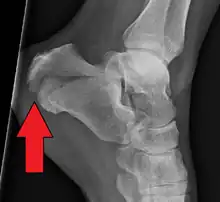

It usually occurs when a person lands on their feet following a fall from a height or during a motor vehicle collision.[2][1] Diagnosis is suspected based on symptoms and confirmed by X-rays or CT scanning.[1]

Conventional radiography is usually the initial assessment tool when a calcaneal fracture is suspected. Recommended x-ray views are (a) axial, (b) anteroposterior, (c) oblique and (d) views with dorsiflexion and internal rotation of the foot. However, conventional radiography is limited for visualization of calcaneal anatomy, especially at the subtalar joint. A CT scan is currently the imaging study of choice for evaluating calcaneal injury and has substituted conventional radiography in the classification of calcaneal fractures.[13] Axial and coronal views are obtained for proper visualization of the calcaneus, subtalar, calcaneocuboid and talonavicular joints.

The Angle of Gissane, or "Critical Angle", is the angle formed by the downward and upward slopes of the calcaneal superior surface. On a lateral radiograph, an angle of Gissane > 130° suggests fracture of the posterior subtalar joint surface. Böhler's angle, or the "Tuber Angle", is another normal anatomic landmark seen in lateral radiographs. It is formed by the intersection of 1) a line from the highest point of the posterior articular facet to the highest point of the posterior tuberosity, and 2) a line from the former to the highest point on the anterior articular facet. Böhler's angle is normally 25° to 40°.[14] It is named after Austrian physician Lorenz Böhler.[16] A decreased angle is indicative of a calcaneal fracture.